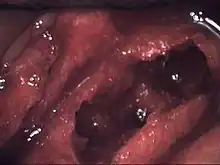

![]() | |

Osteonecrosis of the jaw of the upper left jaw in a patient diagnosed with chronic venous insufficiency | |